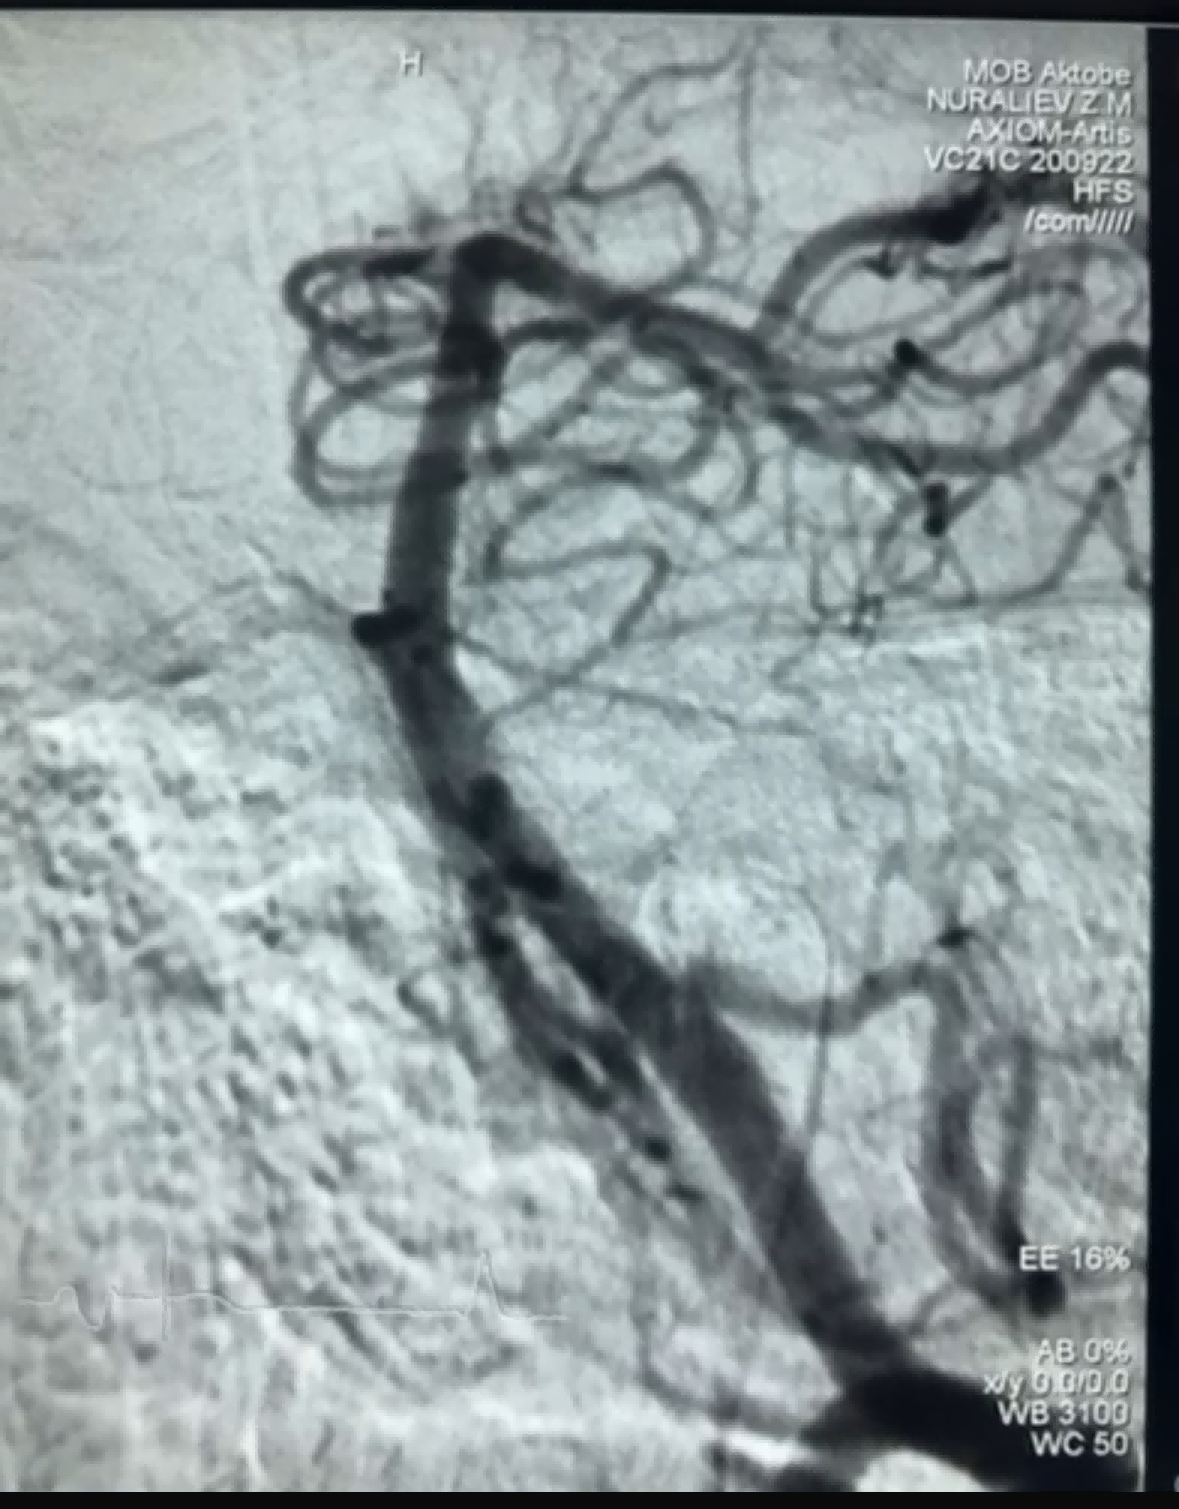

Äskettäin tehtiin onnistunut trombektomiatapaus, jossa käytettiin NeuroSafe Medical Co., Ltd:n Dredger Stent Retriever -laitetta. Dredger Stent Retrieverissä on ei-invasiivinen pehmeä kärki, joka vähentää huomattavasti sisäkalvovaurion riskiä, ja siinä on ainutlaatuinen erikoismuotoinen reikä. malli, joka vangitsee verihyytymät pääasiassa kiristämällä aukon muutokset.